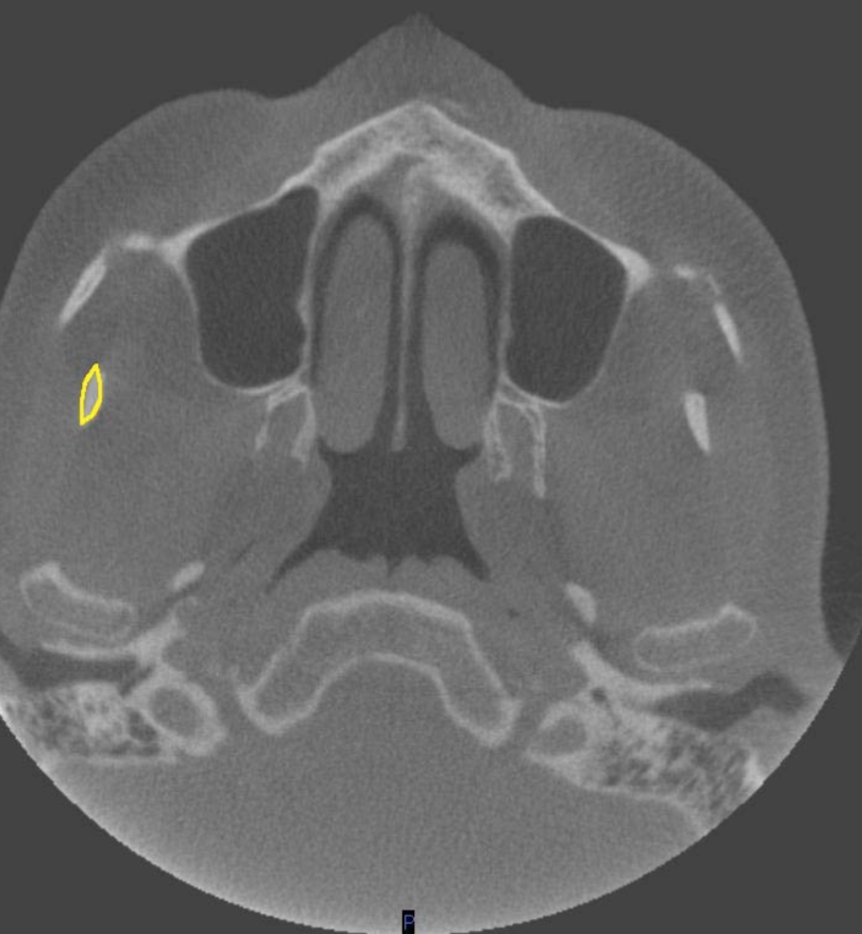

zygomatic arch

what is indicated by the YELLOW